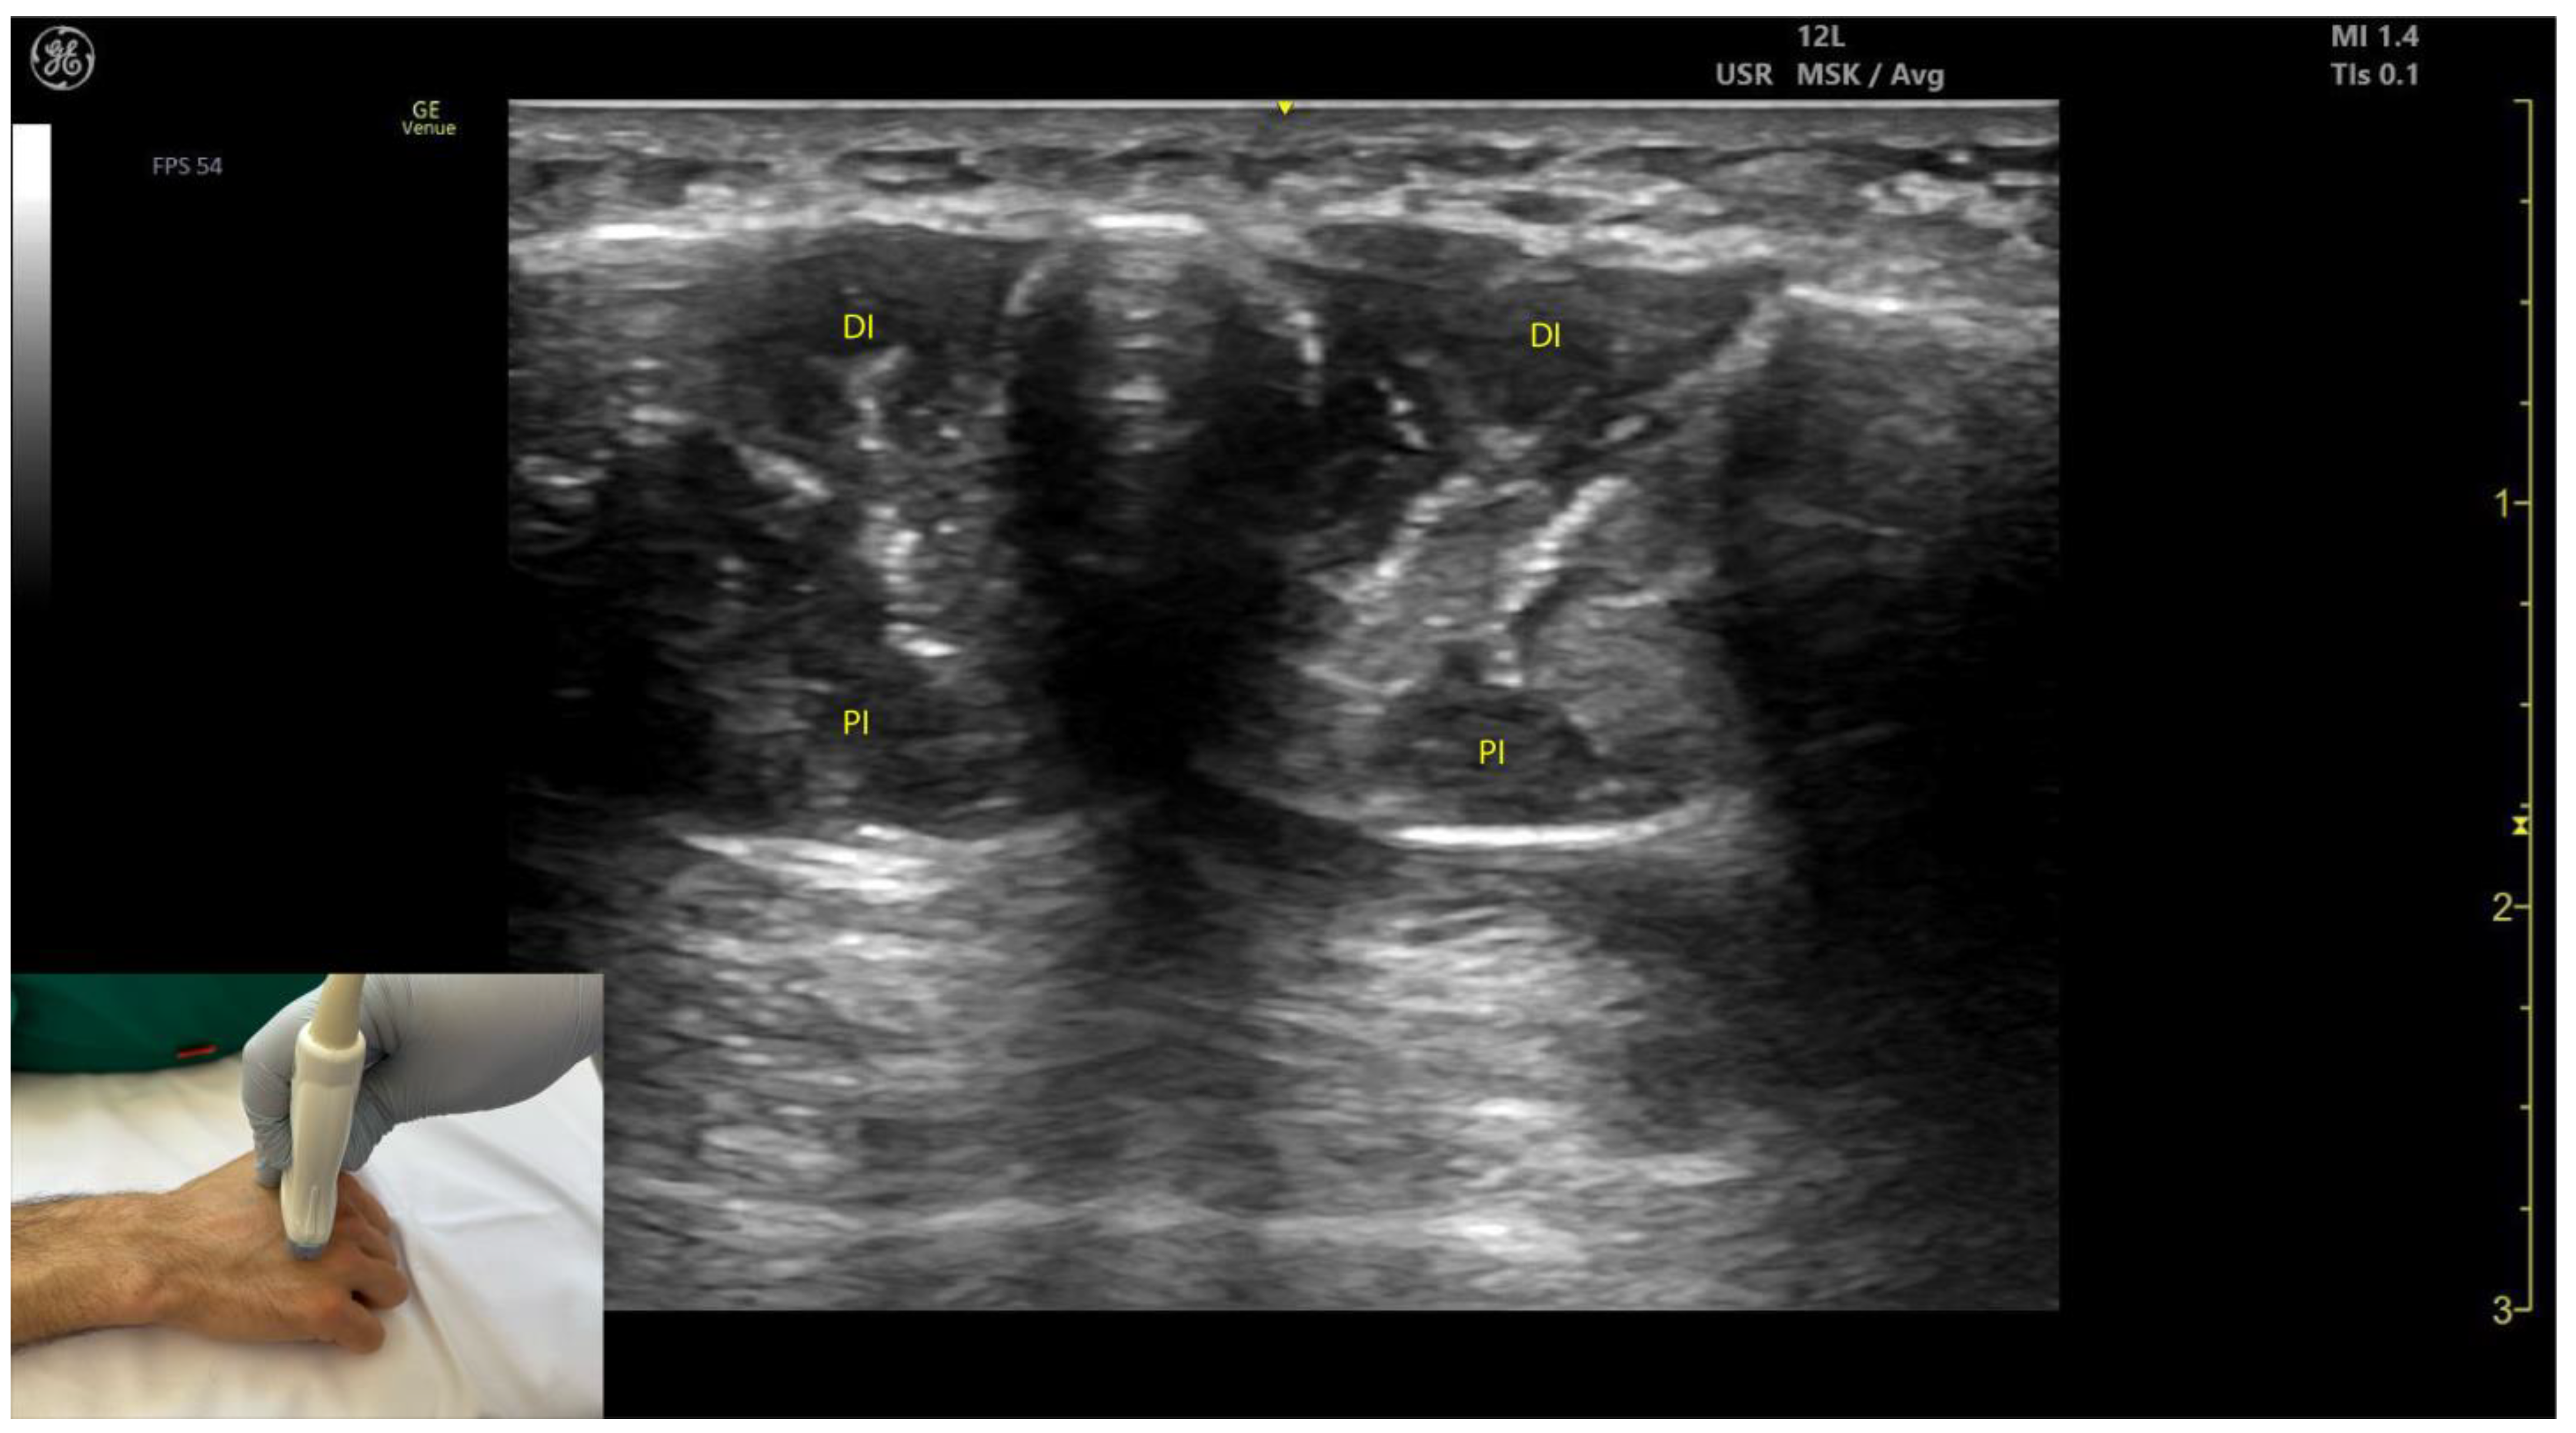

2.13.3. Key Ultrasound Landmarks [60,67,70] (Figure 13)

- Muscle position: The dorsal interossei are the most superficial muscle structures on the dorsal aspect of the hand.

- Muscle morphology: The dorsal interossei are bipennate muscles, whereas the palmar interossei are unipennate. Musculoskeletal ultrasound also allows visualization of the intramuscular fascia within these structures.

- External fascia: The interossei muscles lack a pronounced fascia to clearly demarcate the dorsal and palmar interossei (adjacent muscle masses), which can make precise localization during BoNT-A injections more challenging.

- Muscle size: The first dorsal interosseous muscle is larger compared to the other dorsal interossei. Deep to it lies the AP, which decreases in size as the first dorsal interosseous muscle increases during dynamic scanning cranially.

2.13.4. Clinical Implications and Injection Strategy